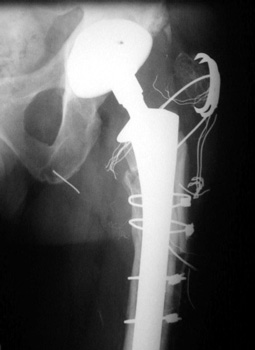

Non union of greater trochanteric osteotomy with broken and frayed cerclage cable. Note broken piece of cerclage cable has migrated toward ischial tuberosity.